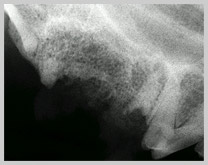

Retained root tip from extracted upper premolar 4